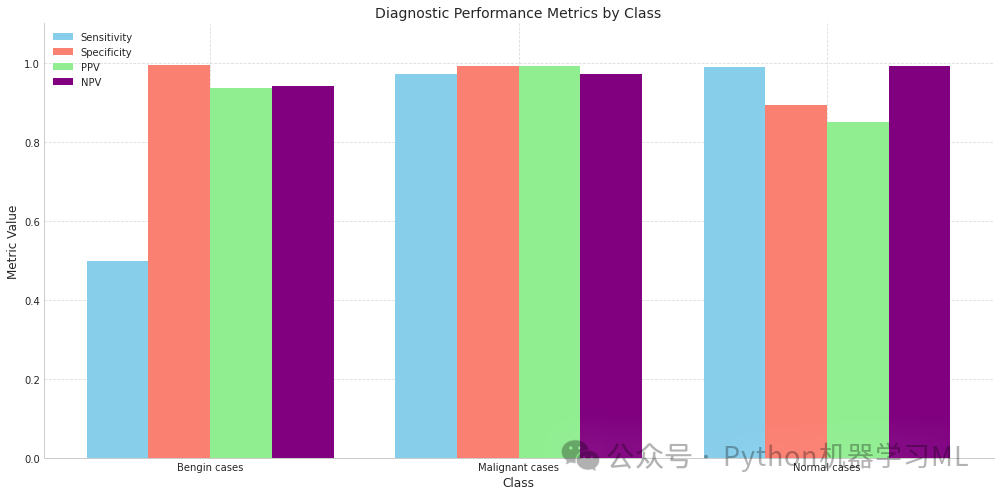

第二阶段:诊断性能比较柱状图

这个阶段的代码创建了一个柱状图,用于比较不同类别在各种诊断性能指标上的表现。

python# 2. 绘制诊断性能比较图 - 修正以确保数组具有兼容的形状

plt.figure(figsize=(14, 7)) # 创建一个14x7大小的图形

x = np.arange(len(categories)) # 创建类别索引数组

width = 0.2# 设置柱状图宽度

# 确保所有数组与x具有相同的长度

sens_array = sensitivities_array # 使用上面校正后的敏感度数组

spec_array = specificities_array # 使用上面校正后的特异度数组

ppv_array = ppvs_array # 使用上面校正后的PPV数组

npv_array = np.array(npvs) # 将NPV列表转换为numpy数组

# 如果需要,调整npv_array大小

iflen(npv_array) != len(x): # 如果NPV数组长度与类别数量不一致

npv_array = np.resize(npv_array, len(x)) # 调整NPV数组大小

# 绘制柱状图

plt.bar(x - width*1.5, sens_array, width, label='Sensitivity', color='skyblue') # 绘制敏感度柱状图

plt.bar(x - width/2, spec_array, width, label='Specificity', color='salmon') # 绘制特异度柱状图

plt.bar(x + width/2, ppv_array, width, label='PPV', color='lightgreen') # 绘制PPV柱状图

plt.bar(x + width*1.5, npv_array, width, label='NPV', color='purple') # 绘制NPV柱状图

# 设置图表属性

plt.xlabel('Class', fontsize=12) # 设置x轴标签

plt.ylabel('Metric Value', fontsize=12) # 设置y轴标签

plt.title('Diagnostic Performance Metrics by Class', fontsize=14) # 设置图表标题

plt.xticks(x, categories) # 设置x轴刻度标签为类别名称

plt.ylim(0, 1.1) # 设置y轴范围从0到1.1

plt.legend() # 添加图例

plt.grid(True, linestyle='--', alpha=0.7) # 添加网格线

plt.tight_layout() # 调整布局

plt.show() # 显示图形

全面的医学图像分类模型评估工具,分为三个主要阶段:

诊断性能比较柱状图:使用分组柱状图直观比较不同类别在各项诊断指标上的表现差异,便于识别模型在哪些类别上表现更好或更差。